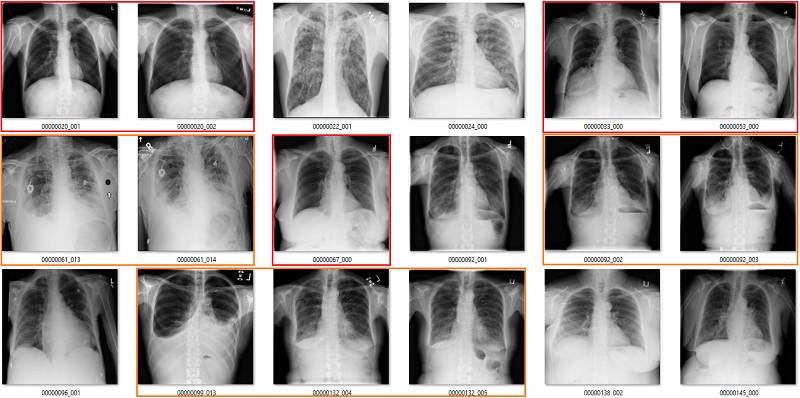

这部分要说该数据集中基于标签的图像。它们是随机选取包含 18 张图像的序列集,并非精挑细选。

我尽量保持谨慎,当一个案例模棱两可的时候,我选择标出标签类别。在所有图像中,红色 = 明显错误的标签;橙色 = 怀疑态度,我没有指出这个问题,但是不能排除这种怀疑。(出于临床诊断的习惯 :p)

肺不张(Atelectasis)

心脏扩大(Cardiomegaly)

纤维化(Fibrosis)

我的标签并不完美,其他放射科医生可能对其中的一些标签有疑惑。但是必须明确一点,我的标签和论文/附录中的结果有极大的不同。

我通常喜欢硬数据,因此我尽力量化标签准确率。事实上我发现其中的很多标签都很难定义,因此下表中未列出。我查看了每个类别中的 130 多张图像,根据我的视觉判断计算原始标签的准确率。这个数据量比较适合使用,因为 95% 的置信区间可能再扩大 5% 左右,所以我的误差率可能达到 20% 左右。

我的视觉分析 vs. 论文中的文本挖掘结果

我再次怀疑我的标签到底对不对,尤其是和一队胸部放射科医生的判断结果相比,但是如上表所示,差别也太大了。我认为上表中的数据证明这些标签无法匹配图像中显示的疾病。